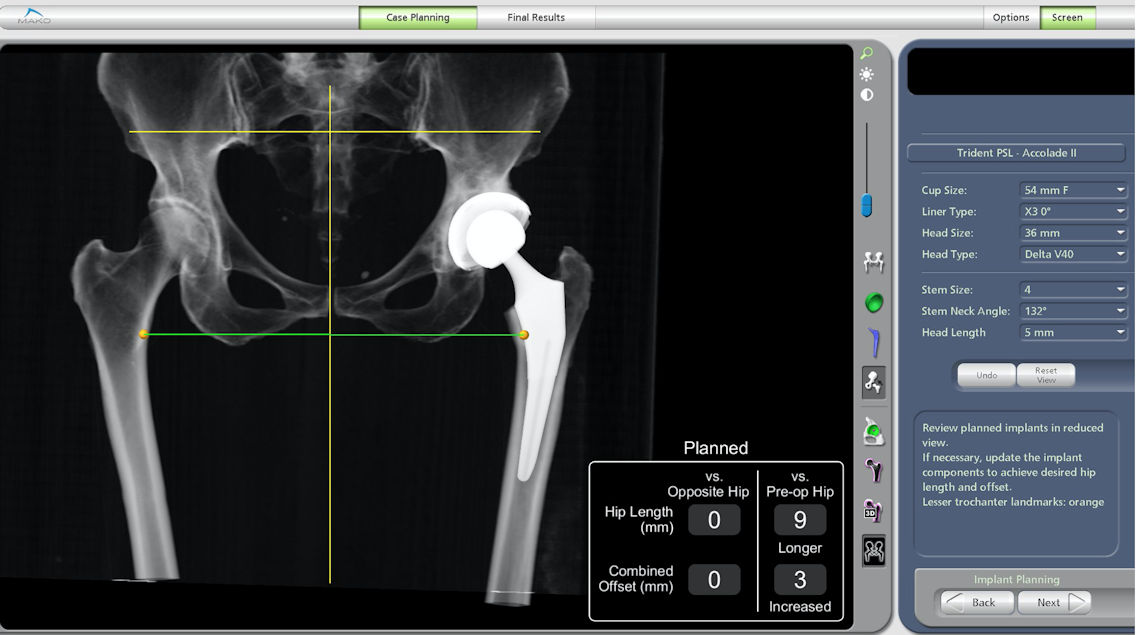

Robotik total kalça protezi öncesinde her iki bacağınızın leğen kemiğini de içine alacak şekilde bilgisayarlı tomografisi çekilir ve 3 boyutlu gerçek vücut modeli oluşturulur. Bu model üzerinde protezin boyutları, uygun yerleşim açıları ve istenen bacak boyu değişiklikleri hesaplanarak bir plan oluşturulur (Resim 1). Doktorunuz ameliyat öncesi bu planı gözden geçirerek son hassas ayarlamaları yapar ve bu plan robota yüklenir. Ameliyata başlamadan önce, protezinizin yerleşimi ve günlük yaşam hareketleri sırasında protez parçaları ve kemikler arasında bir sıkışma ve çarpma olup olmayacağı bir kez daha kontrol edilir. Bunun için robotik sistemde bulunan simülasyon programı ile protez parçaları ve vücut kemikleri arasında oturma, sandalyeden kalkma, yatma ve yürüme sırasında bir sıkışma ve çarpma olup olmadığı, değişik bacak açılarında test edilir. Robotik sistemde protez parçaları veya kemikler arasında istenmeyen bir temas var ise, ya protez yerleşimi değiştirilir ya da ameliyat sırasında temas eden kemik kısım traşlanır. Bu sayede, standart kalça protezi sonrası % 2 civarında görülebilen protezin yerinden çıkması riski en aza indirilebilir.

Resim 1: Ameliyat öncesi planlama ile protezin boyutu, yerleşimi ve kesi açıları belirlenir.